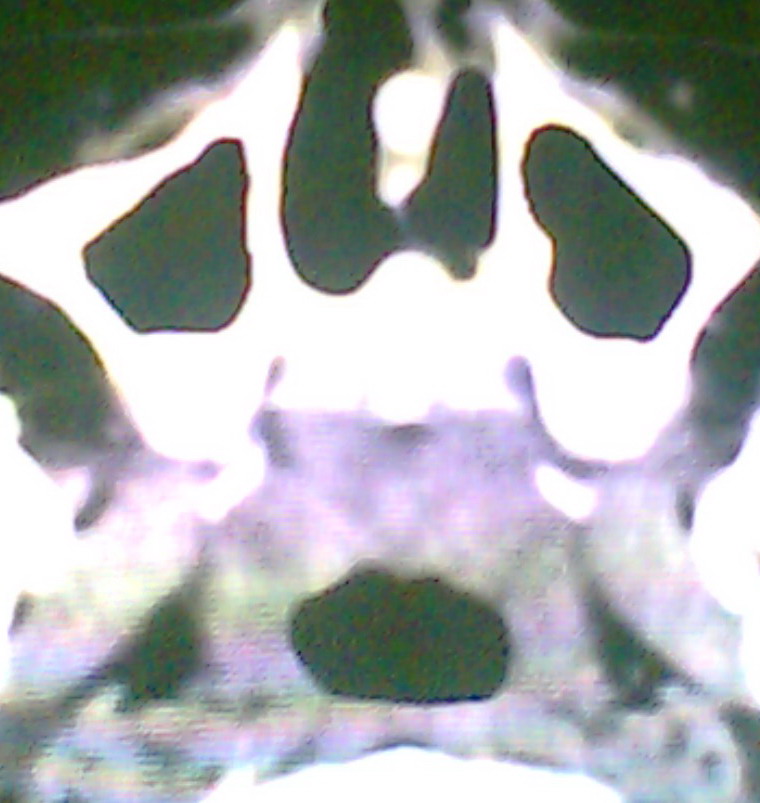

女、18岁,身高1.5左右,鼻塞、流涕数月,两侧瞳孔明显增大,曾与几年前去北京看眼,未发现病变。

考虑起源与蝶窦的粘液囊肿。

支持:考虑起源与蝶窦的粘液囊肿,应该加冠状面扫描

考虑脑膜脑脊液鼻内膨出

考虑起源于蝶窦的粘液囊肿突入鼻咽部。

\"几年前去北京看眼\"不知这句话有何玄机,支持考虑脑膜脑脊液鼻内膨出,膨出口在蝶鞍处

建议冠状面扫描,支持:脑膜鼻内膨出; 蝶窦粘液囊肿突入鼻腔可能性小。

在上级医院冠状位ct扫描后,诊断为:脑膜膨出,已住院准备手术。等待术后结果。